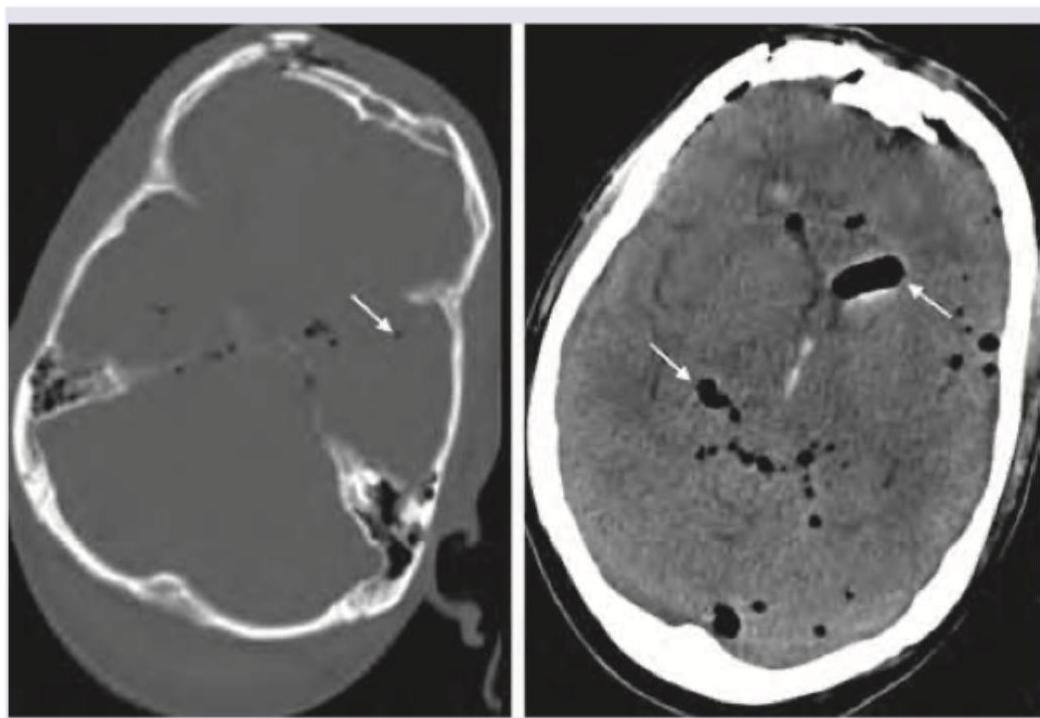

Question 7: A 79-year-old male presented to the emergency department after a facial trauma. The patient had Parkinson's disease and atrial fibrillation and was on treatment with acetylsalicylic acid for AF. The image shows? (Recent NEET Pattern 2016-17)

- A. Hydrocephalus

- B. Pneumocephalus (Correct Answer)

- C. Intraventricular bleed

- D. Subarachnoid hemorrhage

Explanation: ***Pneumocephalus*** - The image clearly shows **intracranial air** (dark areas within the brain parenchyma and ventricles, indicated by arrows) following facial trauma, consistent with **pneumocephalus**. - **Pneumocephalus** often results from fractures of the skull base or paranasal sinuses, especially after trauma, allowing air to enter the intracranial space. *Hydrocephalus* - **Hydrocephalus** involves enlargement of the **ventricles** due to an accumulation of cerebrospinal fluid, which would appear as dark, but *fluid-filled* spaces, not air-filled. - No signs of significantly dilated ventricles are observed; instead, distinct air pockets are visible, which look black on CT. *Intraventricular bleed* - An **intraventricular bleed** would appear as **hyperdense (bright)** material (blood) within the ventricles on a CT scan, which is not seen here. - The appearance of the abnormalities is **hypodense (black)**, indicating air, not blood. *Subarachnoid hemorrhage* - **Subarachnoid hemorrhage** is characterized by **hyperdense (bright)** blood filling the subarachnoid spaces, particularly the sulci and basal cisterns. - The image displays **hypodense** areas consistent with air within the brain, not diffuse bright areas of blood in the subarachnoid space.